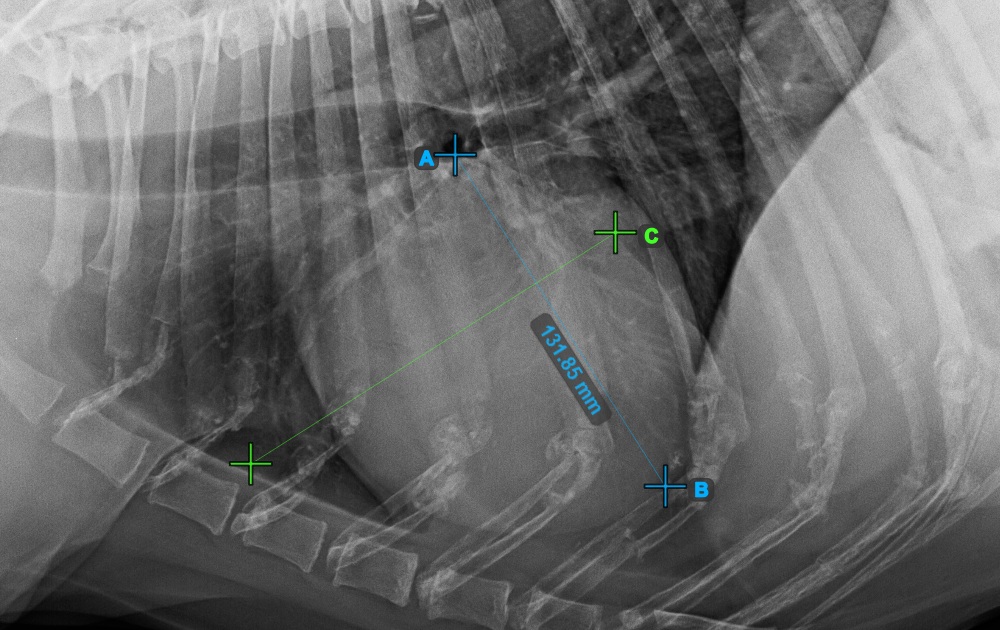

Continue the measurement by marking the widest right (cranial) point of the short axis of the heart.

The image below represents a typical placement of the most cranial point on the short axis of the heart.